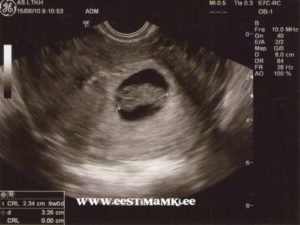

На протяжении беременности каждая женщина должна пройти три плановых УЗИ. Срок проведения плановых исследований:

• первое УЗИ назначается на срок от 10 до 12 недель;

• второе УЗИ проводят, когда срок беременности составит от 18 до 22 недель;

• третье УЗИ нужно будет пройти ближе к родам, когда срок составит от 33 до 35 недель.

Помимо плановых УЗИ могут быть назначены и дополнительные, если появятся показания.

Совет! Проведение УЗИ не оказывает отрицательного влияния на плод, поэтому будущие мамы не должны бояться, если врач рекомендует пройти дополнительное обследование.

Стоит ли делать УЗИ на 9 неделе? Ведь первое плановое обследование назначают не ранее 10 недели? Ответить на эти вопросы сможет только врач. Возможно, он перенесет УЗИ на неделю, когда срок беременности достигнет 10 недель. А может быть порекомендует не ждать 10 недели, а пройти обследование немедленно. Как правило, УЗИ ранее 10 недели назначают:

• при подозрении на внематочную беременность;

• для подтверждения или исключения многоплодной беременности;

• для выявления патологий плода, плаценты, матки;

• подозрение на то, что беременность перестала развиваться.

Если же особых показаний нет, то врач, как правило, рекомендует дождаться 10 недели и пройти плановое исследование. Но даже в том случае, если врач не советует ждать наступления 10 недели, будущая мать не должна пугаться.

Внеплановое исследование вполне может подтвердить, что с плод развивается нормально. То есть, оно нужно еще и для того, чтобы будущая мама перестала волноваться. Ведь нервозность матери отрицательно влияет на развитие плода.